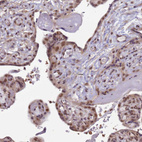

Immunohistochemical staining of human skin shows strong nuclear positivity in squamous epithelial cells.